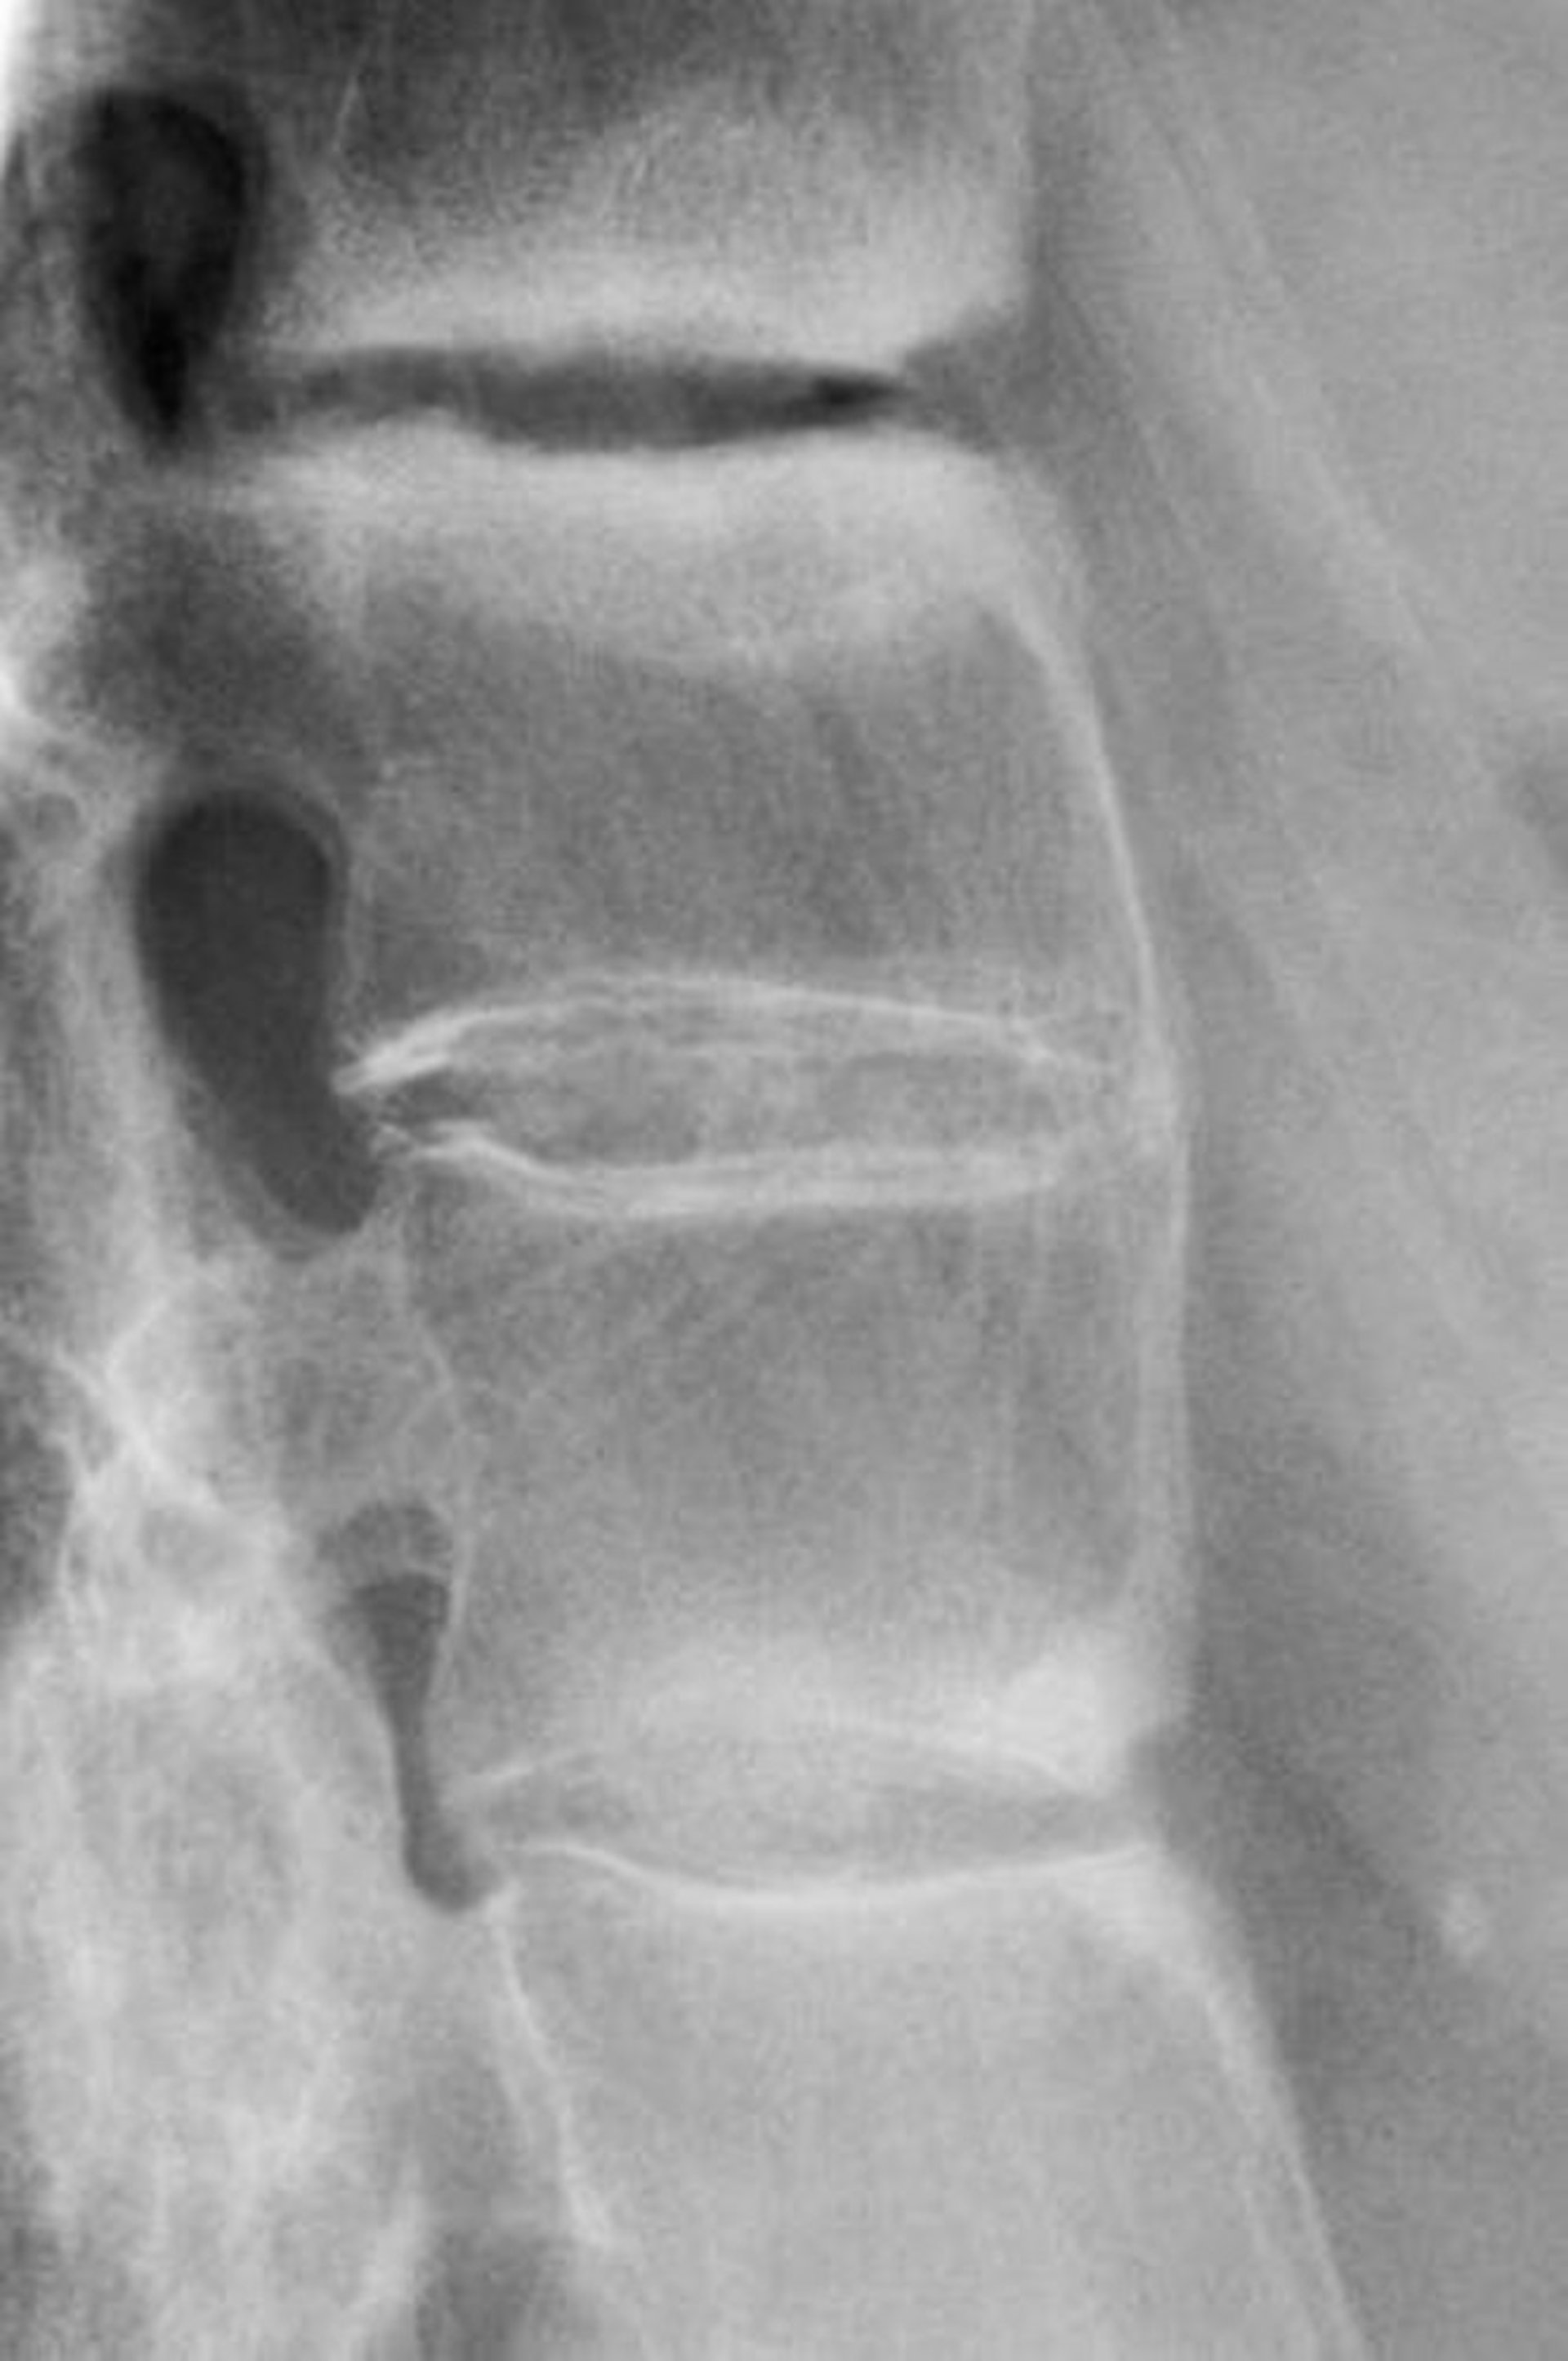

This radiograph shows sclerosis between lumbar vertebrae, loss of lordosis, and fusion of lumbar vertebrae, a finding indicating advanced ankylosing spondylitis.